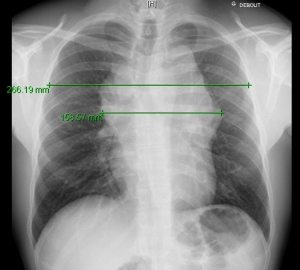

Mesure Du Rapport Mt Sur Radio Thorax Lymphoma Care